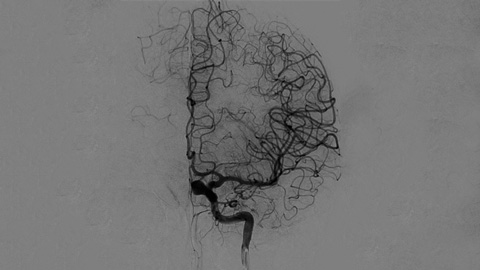

Klinische Anwender verlassen sich auf die klassische DSA-Bildgebung als wichtigste Informationsquelle während des gesamten Eingriffs.